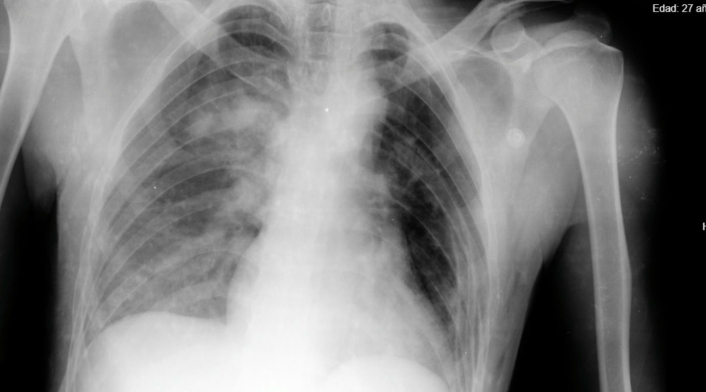

Una herida con arma cortopunzante estuvo a centímetro y medio de perforar el corazón de Deyson Peñaloza de 27 años, quien se desempeña como auxiliar de mantenimiento.

“El paciente ingresó inconsciente y con 98 % de probabilidades de morir, pero luego de la inmediata atención y valoración que recibió el joven, tras salir del área de reanimación, fue llevado a sala de cirugía donde se intervino de manera exitosa”, comentó Josef Kling, médico especialista de cirugía general de la Subred Sur.

Mientras el paciente era atendido en el servicio de urgencias, en la unidad transfusional de la Subred Sur se le realizaron pruebas de laboratorio para atender sus hemoderivados y así poder adelantar el procedimiento quirúrgico, dada la condición crítica en la que fue recibido.